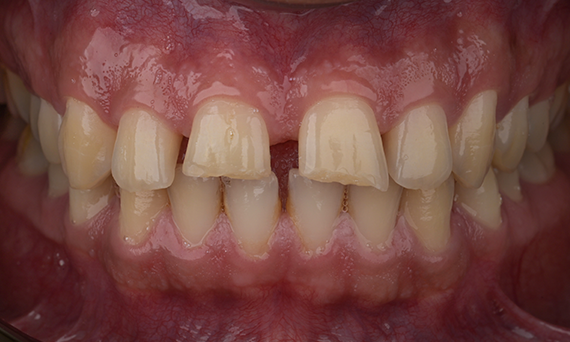

Full mouth rehabilitation with 28 all-ceramic restorations

A particular and protracted case of skeletal Class II malocclusion and generalized amelogenesis imperfecta in a teenager was referred for prosthetic rehabilitation. The aim of the treatment was to prepare the remaining tooth structure, remove undercuts, and make room for all-ceramic crowns covering the entire dentine and simulating the lost enamel.

Before: Initial situation prior to orthodontic treatment.

After: Final result, 1 week post-operative.